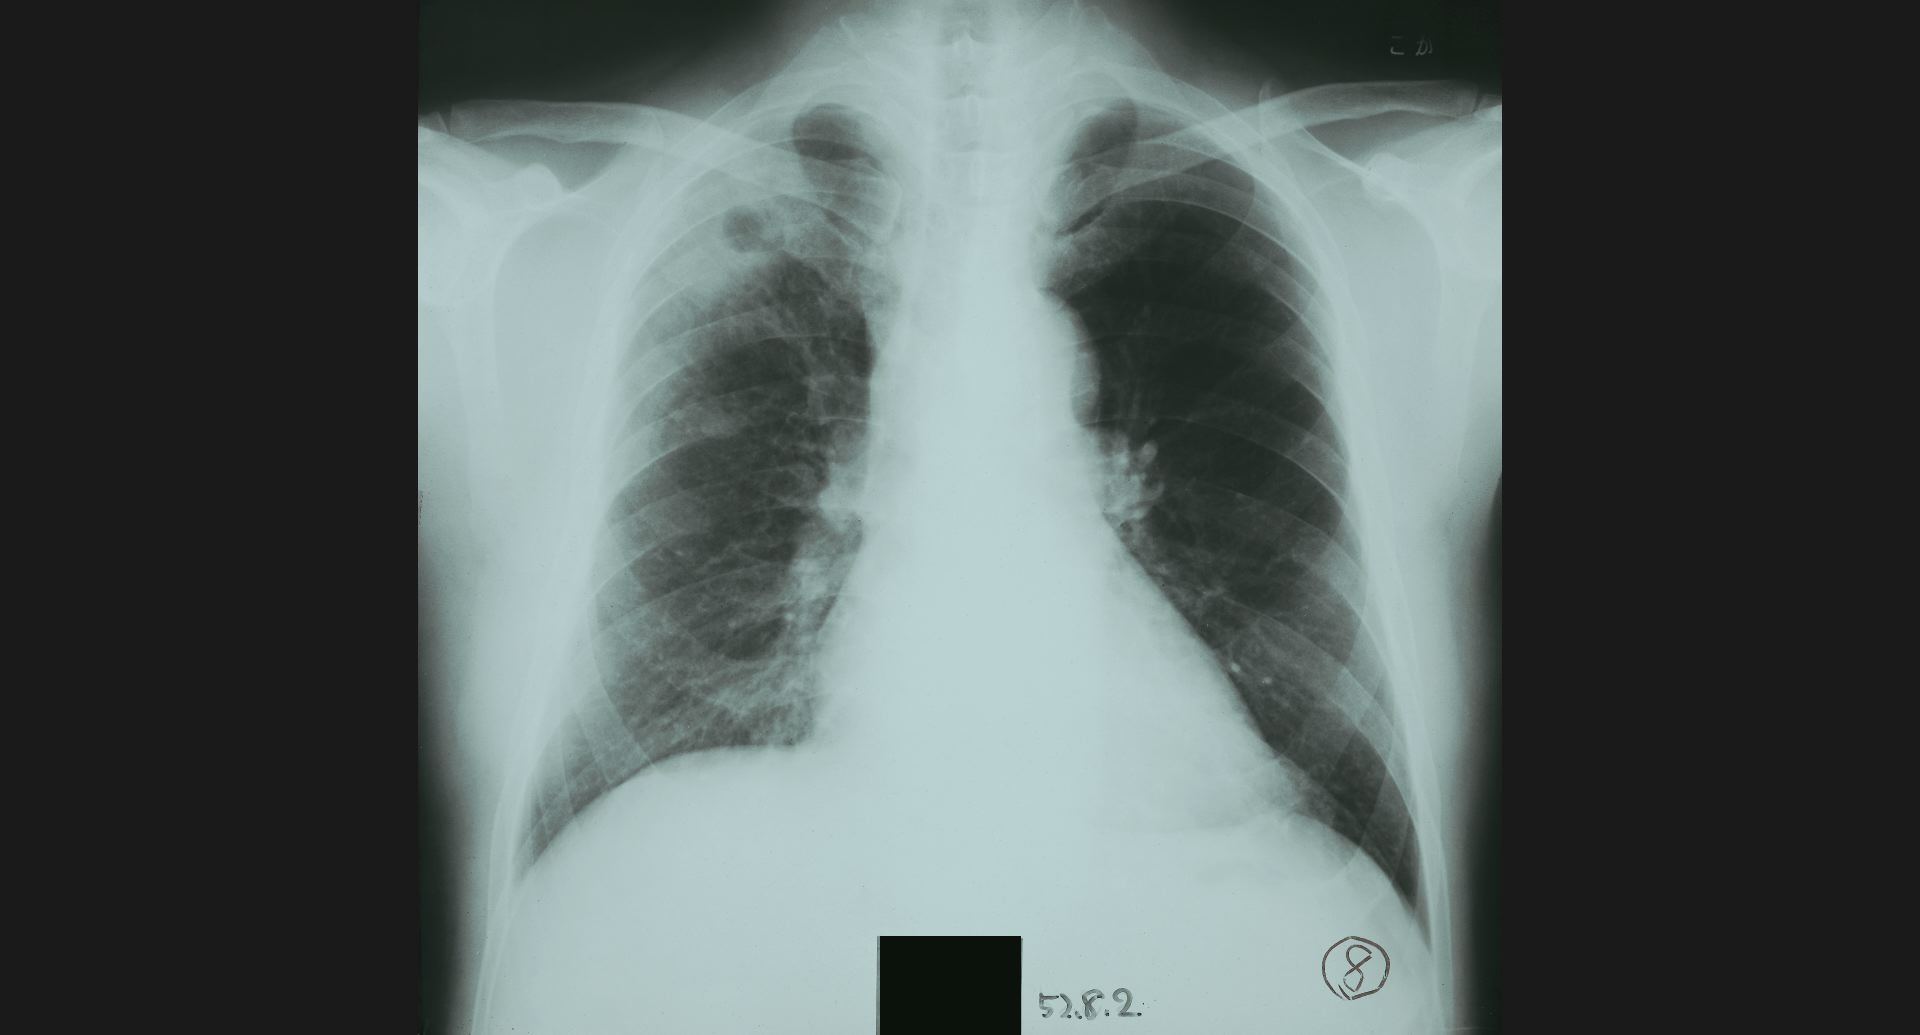

fig.5(93KB) :Post-plomboge chest

ピンポン玉、左肺上葉の細かい石灰巣。